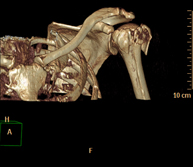

Prueba radiológica que consiste en obtener imágenes del hueso peñasco del temporal (oído interno, medio y externo) de alta definición anatómica mediante el empleo de un equipo de TC (Tomografía Computarizada). Indicaciones: pérdida de audición súbita o crónica, cuadros vertiginosos, mareo, malformaciones congénitas. - Angio – TC Troncos Supraaórticos

Prueba radiológica que consiste en obtener imágenes de las arterias carótidas del cuello de alta definición anatómica mediante el empleo de un equipo de TC (Tomografía Computarizada) y la inyección de contraste intravenoso. Posteriormente, las imágenes son reconstruidas en tres dimensiones (3D). Indicaciones: accidente vascular cerebral agudo, accidente vascular transitorio, soplo carotídeo. - TC Columna cervical